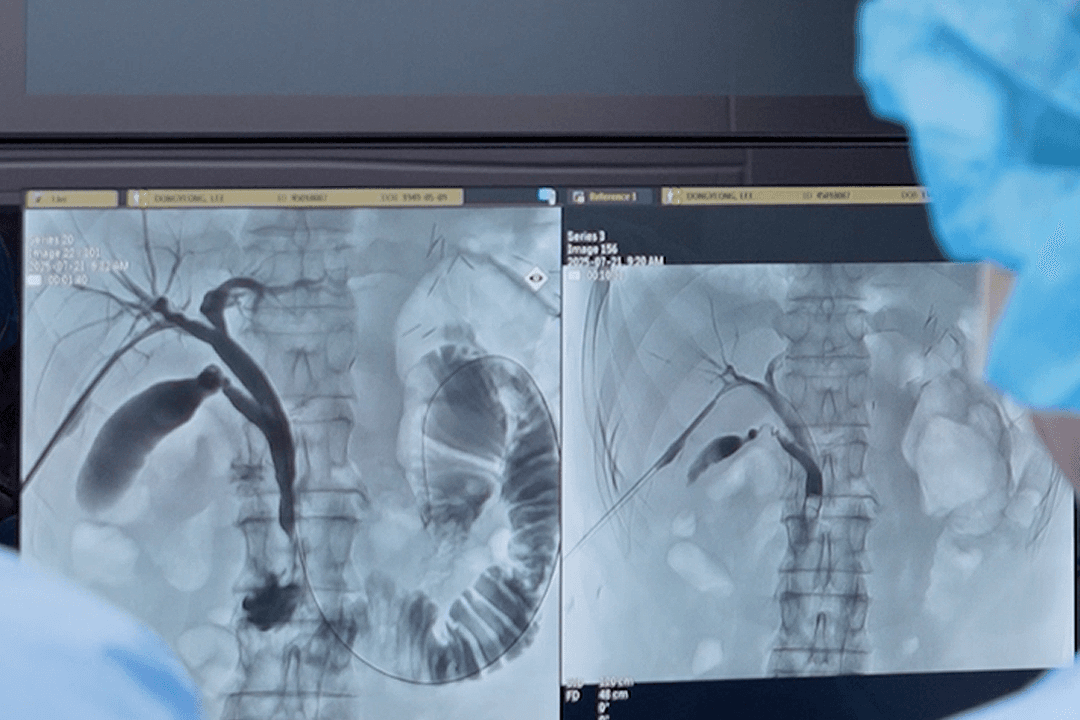

진단부터 항암까지 원스톱 진료를 제공하는 시스템을 구축하고, 최신 복강경 수술 장비를 도입하고 대학병원 출신 의료진을 영입하여 수준 높은 의료 환경을 갖추며 조기진단과 최소침습 치료의 역량을 강화했습니다.